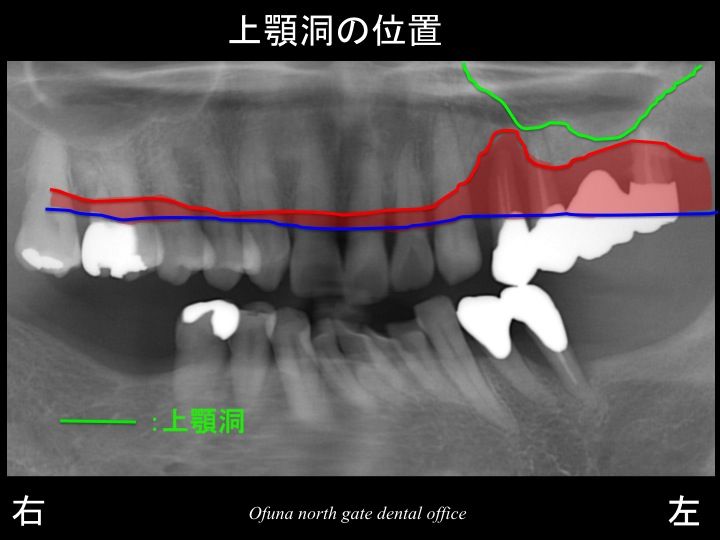

さらに問題があったのが、上顎洞の状態です。

以下の緑線は上顎洞という空洞です。

骨ではなく、穴が開いているのです。

いつもこのブログをご覧になっている方はもうすでにご存知のことと思います。

上顎洞の詳細は、以下を参考にして下さい。

上顎洞

分かりやすいように上顎洞 の領域を緑色で塗りつぶしたのが以下です。

骨吸収が大きい!

上顎洞の状態!

等の問題があるとこで、

インプラントを埋入するための骨の高さが非常に少なくなっています。